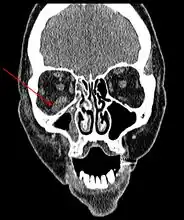

Imaging is often performed, such as CT scan of lungs and sinuses.[38] Signs on chest CT scans, such as nodules, cavities, halo signs, pleural effusion and wedge-shaped shadows, showing invasion of blood vessels may suggest a fungal infection, but does not confirm mucormycosis.[16] A reverse halo sign in a person with a blood cancer and low neutrophil count, is highly suggestive of mucormycosis.[16] CT scan images of mucormycosis can be useful to distinguish mucormycosis of the orbit and cellulitis of the orbit, but imaging may look identical to those of aspergillosis.[16] MRI may also be useful.[39]

CT head (axial): invasion of right maxillary sinus (presented with double vision, swollen painful eye).

CT head (coronal) of same person.